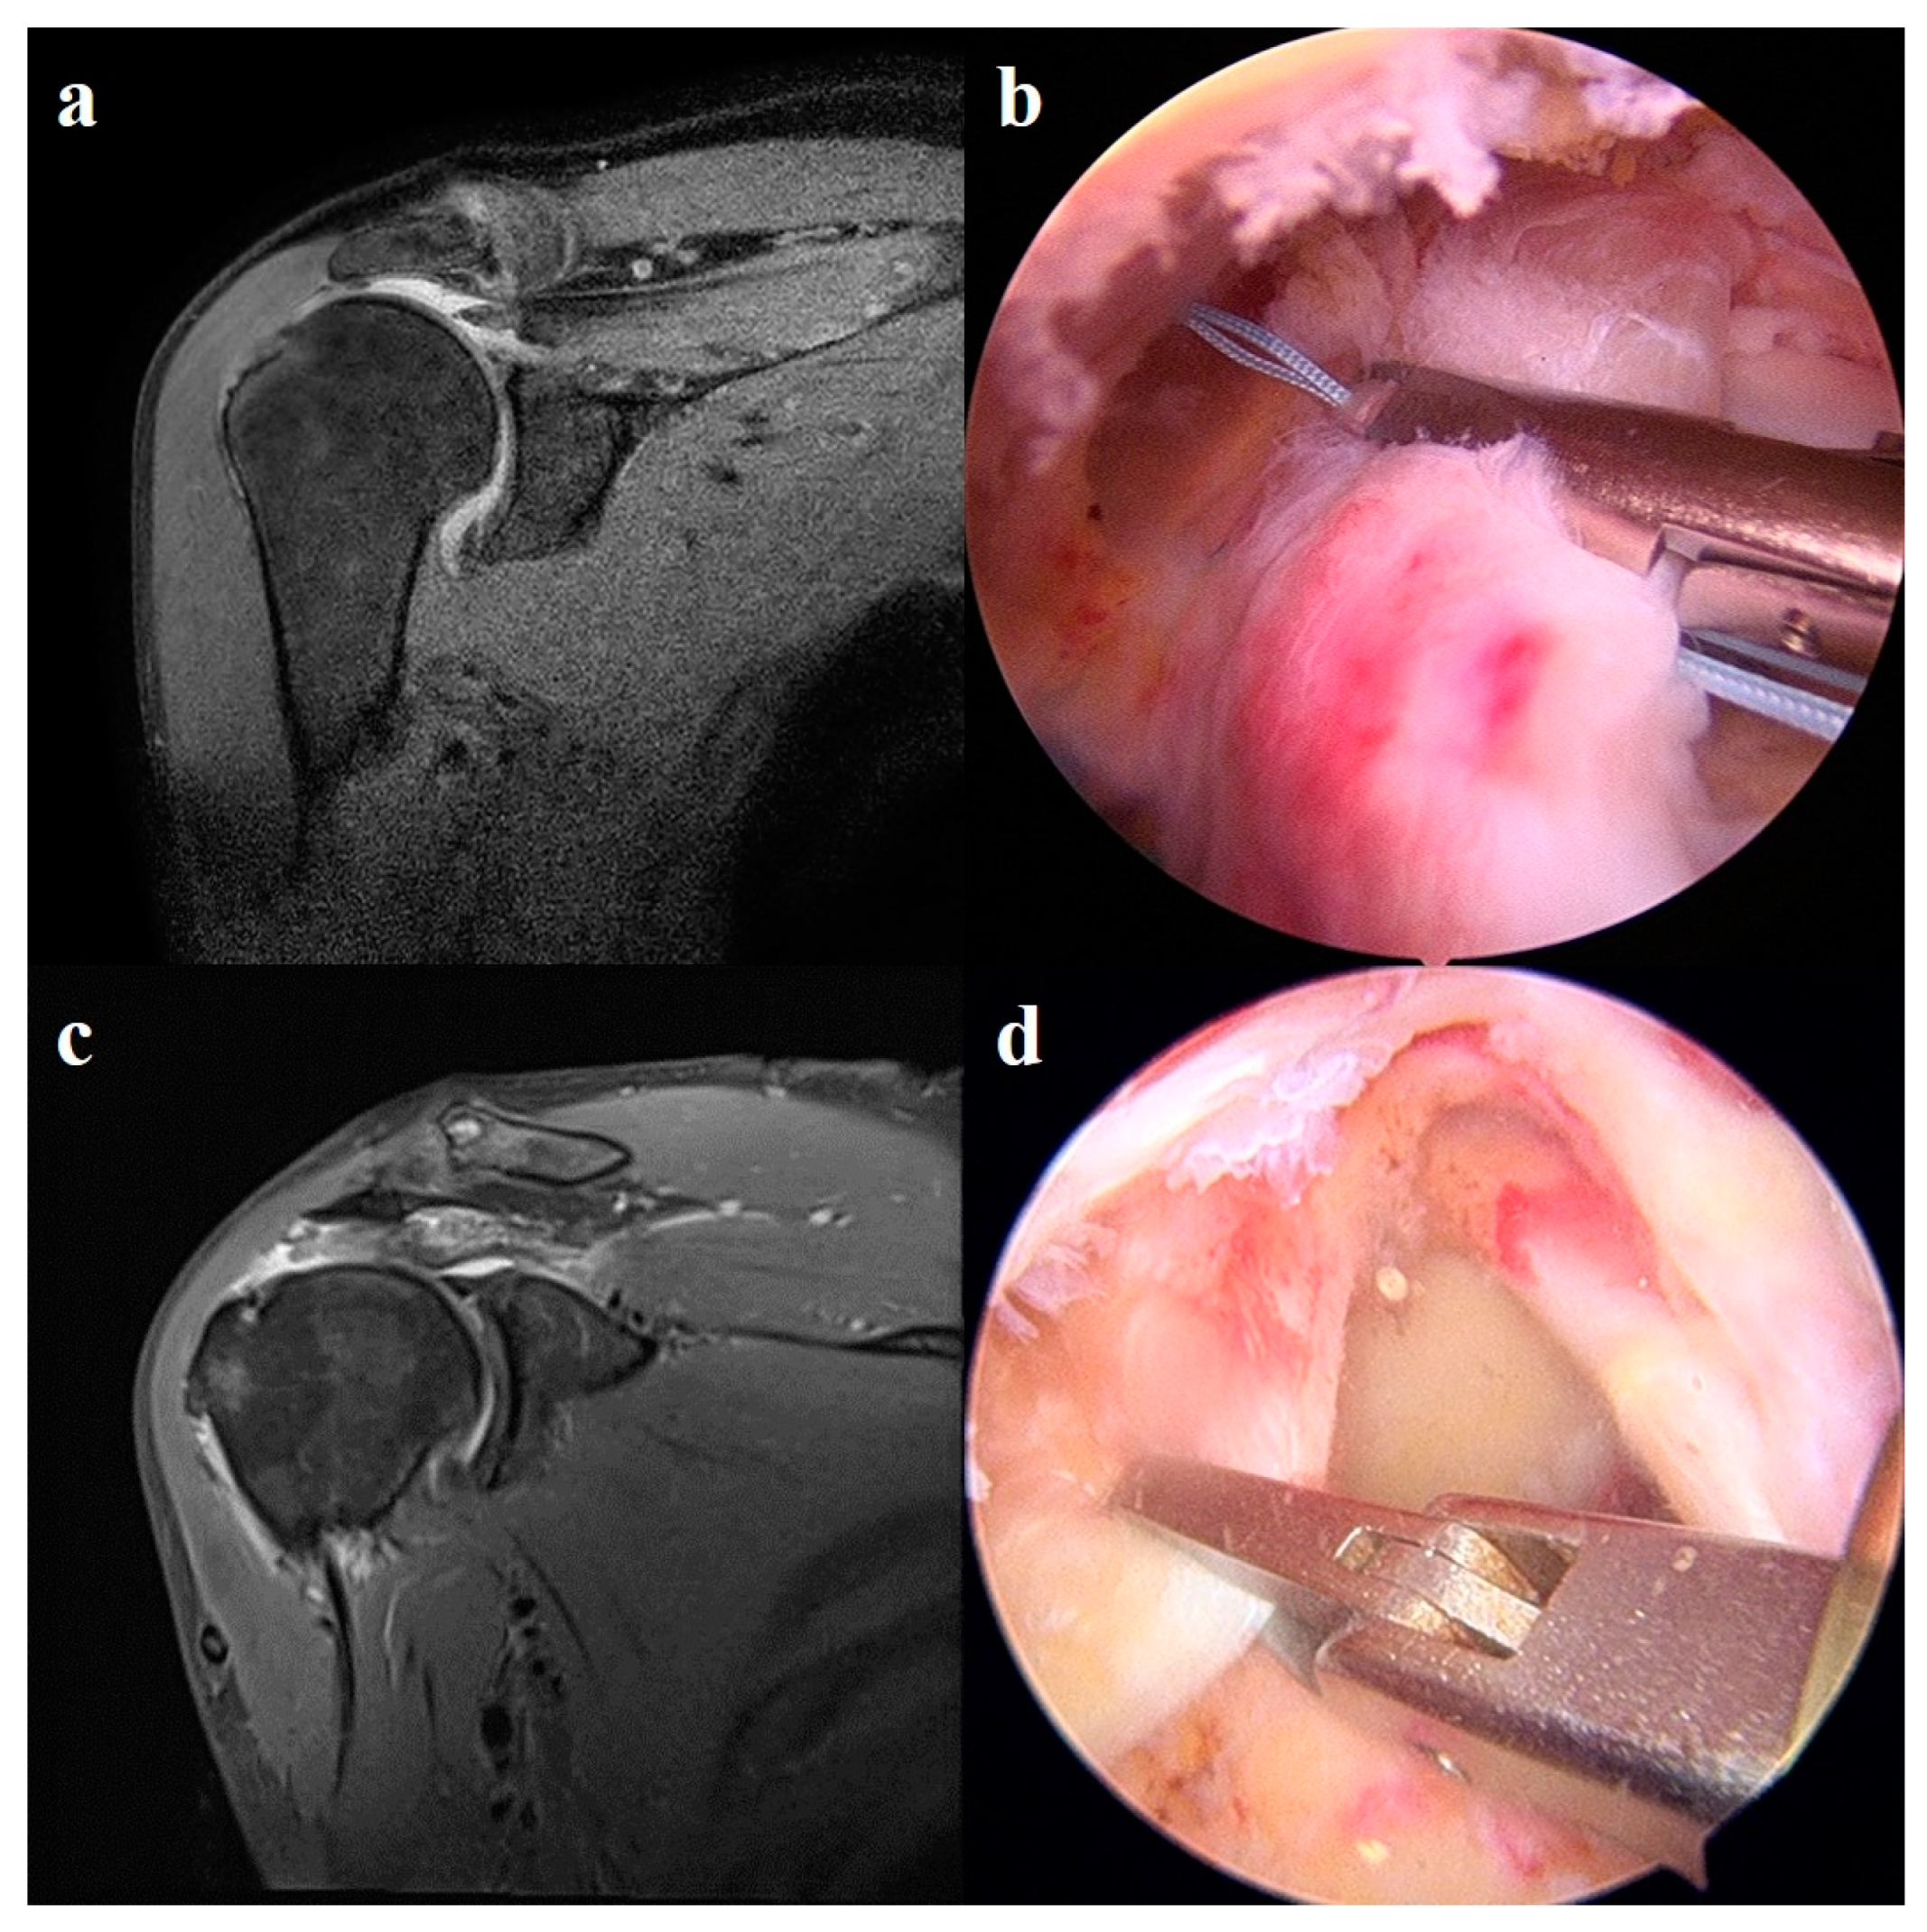

2.5.2. Superior Capsule Reconstruction

2.5.3. Patch Graft Augmentation